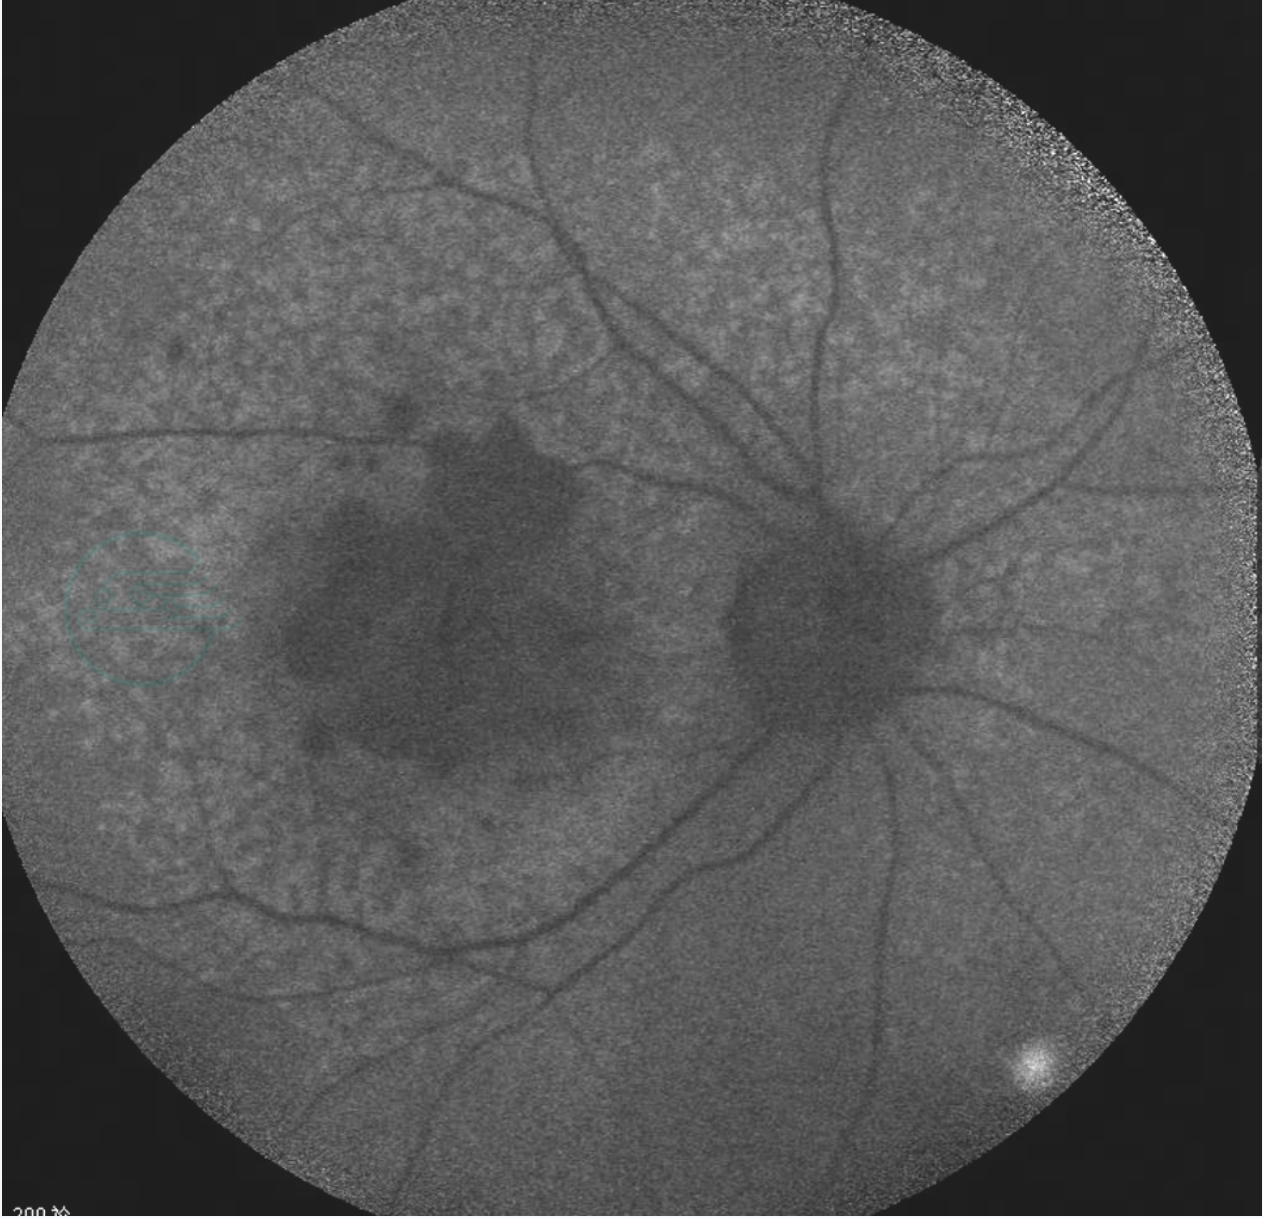

图3 干性AMD吲哚青绿眼底血管造影

可见脉络膜毛细血管萎缩区中暴露深层脉络膜大血管